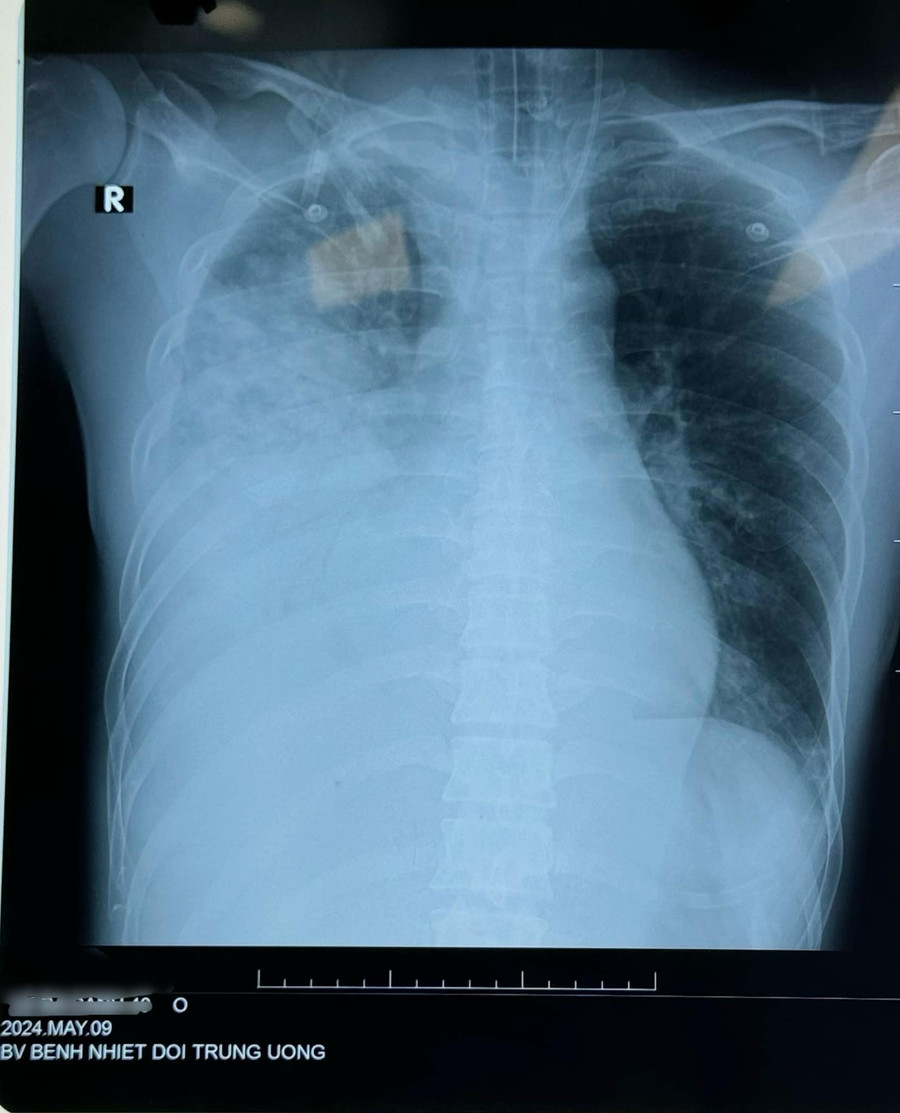

Cách vào viện 5 ngày, bệnh nhân xuất hiện sốt cao, hắt hơi, sổ mũi, ăn uống kém. Khi thấy khó thở đau tức ngực sau xương ức, khó thở tăng dần, ho khạc đờm xanh bệnh nhân nhập viện được test cúm B (+) .

Khi chụp cắt lớp có hình ảnh tổn thương phổi bên phải, được chẩn đoán: Viêm phổi nặng - Cúm B.

Bệnh nhân được thở O2 mask và chuyển đến Bệnh viện bệnh Nhiệt đới Trung ương. Bệnh nhân nhập trong tình trạng khó thở và tức ngực nhiều, sau đó được đặt ống thở máy. Hiện tại bệnh nhân đã được đặt ECMO.